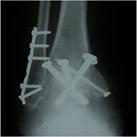

When conservative (non-operative) measures such as activity modification, painkillers and orthotic supports are no longer adequate, surgery may become necessary. Ankle or other hind foot joint stiffening operation (fusion or arthrodesis, Fig 2) has been the surgery of choice and can be performed both as an open and as a keyhole procedure. The trade-off is pain reduction for increased stiffness but other than in the knee or hip joint fusion is relatively well tolerated and the functional results are surprisingly good. More recently results from modern ankle replacing prostheses (Fig 3) have been improving, offering this as a suitable alternative for selected patients.